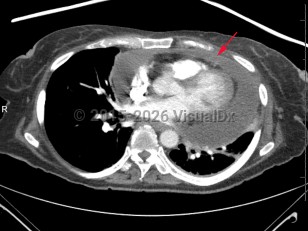

The signs and symptoms of tamponade are nonspecific and are present in a variety of clinical scenarios. Primary symptoms of cardiac tamponade include dyspnea, chest pain, jugular venous distension, and tachycardia. Systemic blood pressure is often normal until severe tamponade is present due to compensatory changes of increased systemic vascular resistance. Tachypnea results from compensatory responses due to tissue hypoperfusions rather than as a primary pulmonary etiology. Other findings include cyanosis, peripheral leg edema, decreased heart sounds, fatigue, syncope, anuria, oliguria, pericardial friction rub, and pulsus paradoxus.

Rapidly accumulating pericardial effusions (eg, from trauma, iatrogenic causes, dissection) are more likely to present with symptoms similar to cardiogenic shock. These patients are likely hypotensive, tachycardic, and tachypneic, with cool extremities and other signs of poor perfusion. Slower growing effusions are more likely to present with shortness of breath, fatigue, relative hypotension, and edema.